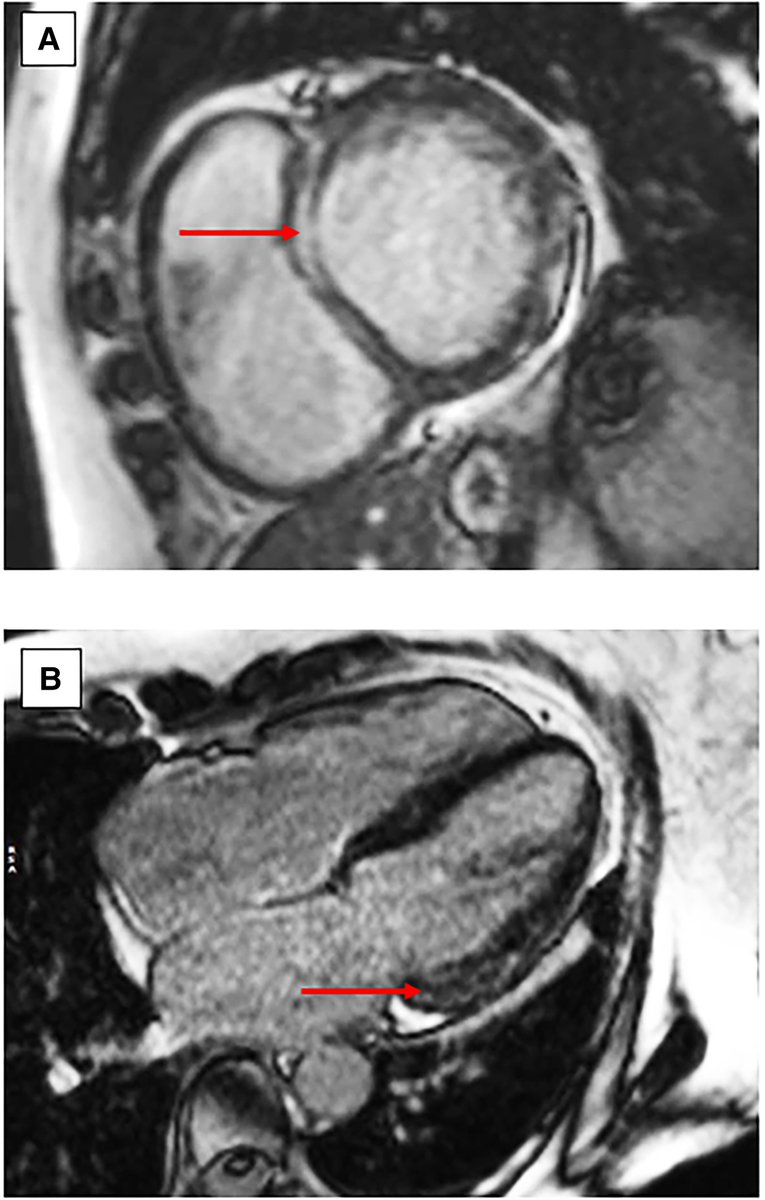

@TJ_Yeo @aayshacader @ANazmiCalik @Phiso_de @ESC_Journals @escardio @ESC_Lavinia #EHJCaseReports poll answer The ECG is consistent with HCM, so all findings are likely (LVH, LV cavity obliteration & LGE) We have a double feature today at @ESC_Journals for this case: https://t.co/RLucrYwGiV Share your cases w us: https://t.co/9qUo9LSsdw

Apical HCM, endomyocardial fibrosis & hypereosinophilic syndrome all in 1 https://t.co/By1yMWgH7m #EHJCaseReports @aayshacader @ANazmiCalik @TJ_Yeo @Phiso_de @EHJCREiC #CardioX #echofirst #whyCMR

#EHJCaseReports poll 1/2 66/M p/w SOB on exertion. ECG as shown (2/2). Nil other significant past medical hx of note. What would you expect to find on #whyCMR? https://t.co/RLucrYxe8t @TJ_Yeo @aayshacader @ANazmiCalik @Phiso_de @ESC_Journals @escardio @ESC_Lavinia